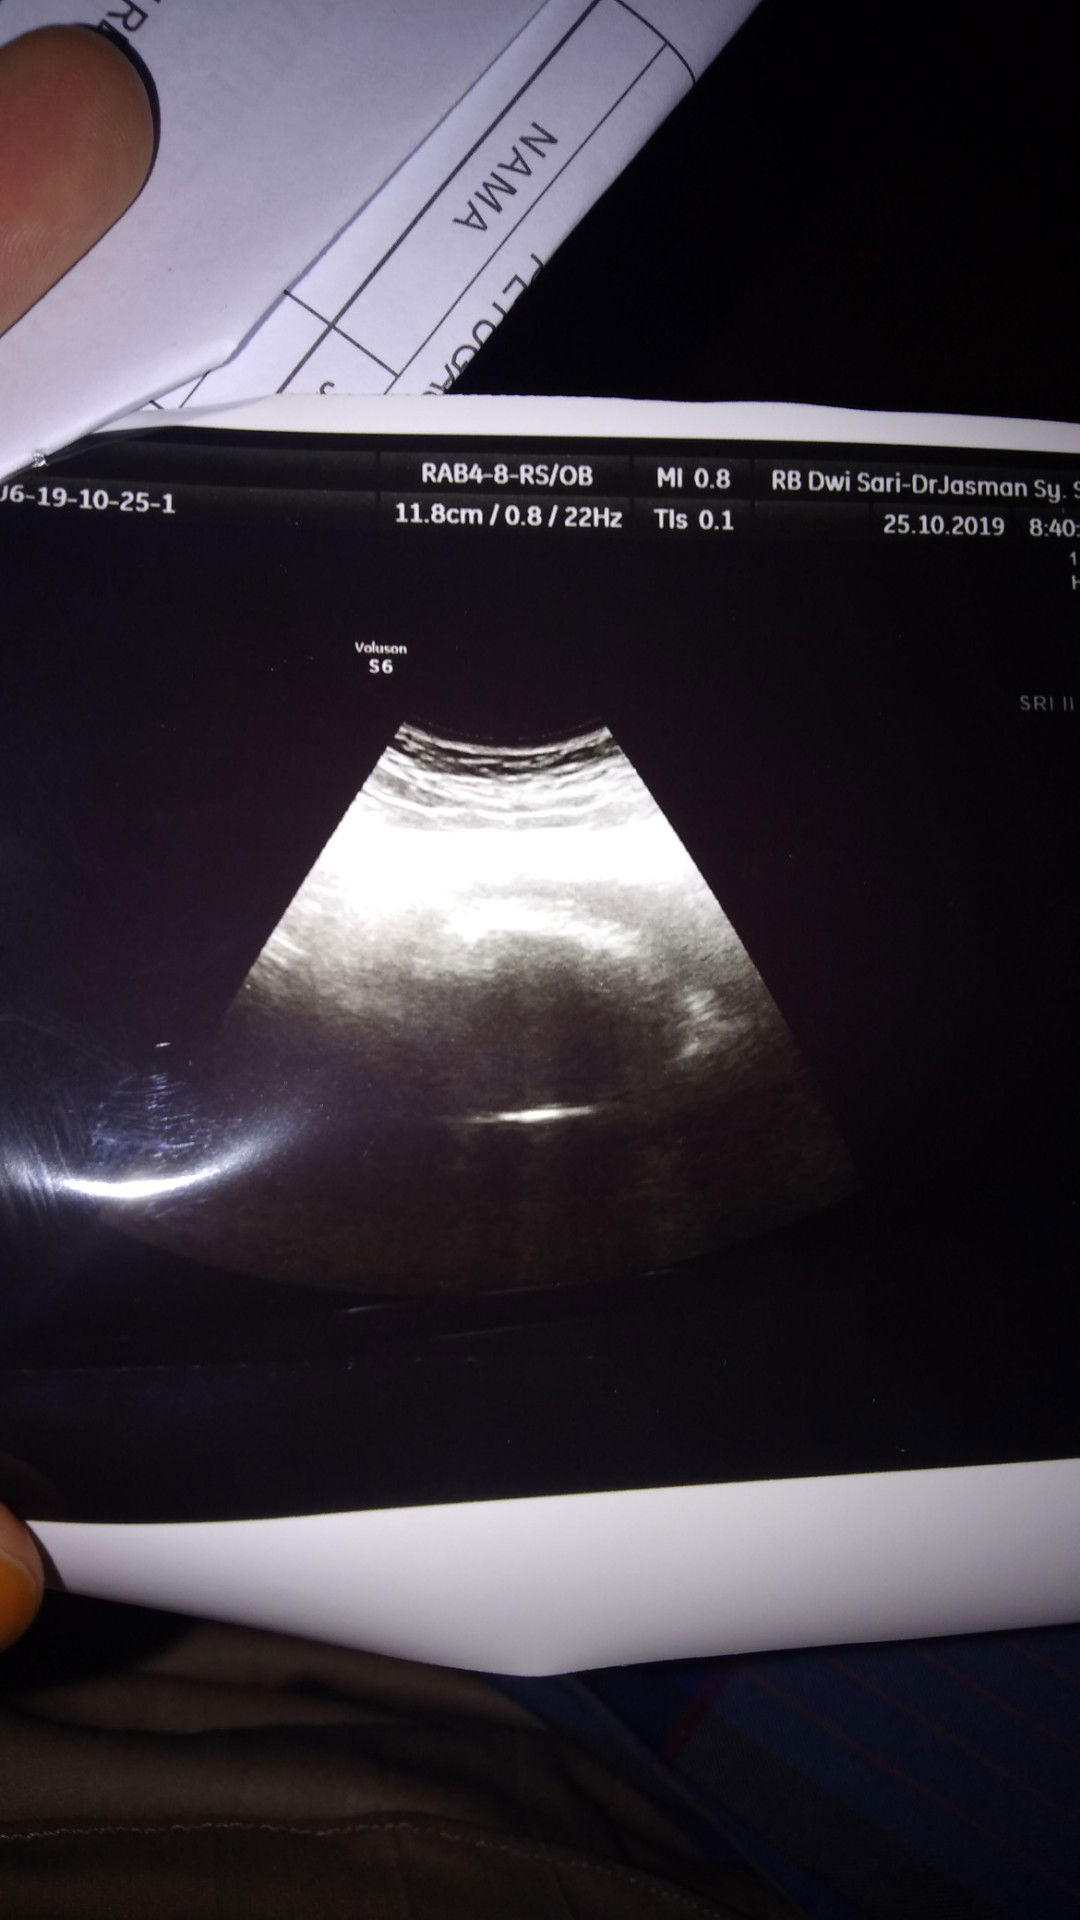

usg pasca keguguran

USG pasca keguguran kata dokter udah bersih tapi masih ada kluar ,,info donk Bun untuk bersih i rahim pakai apa,ini hasil USG saya